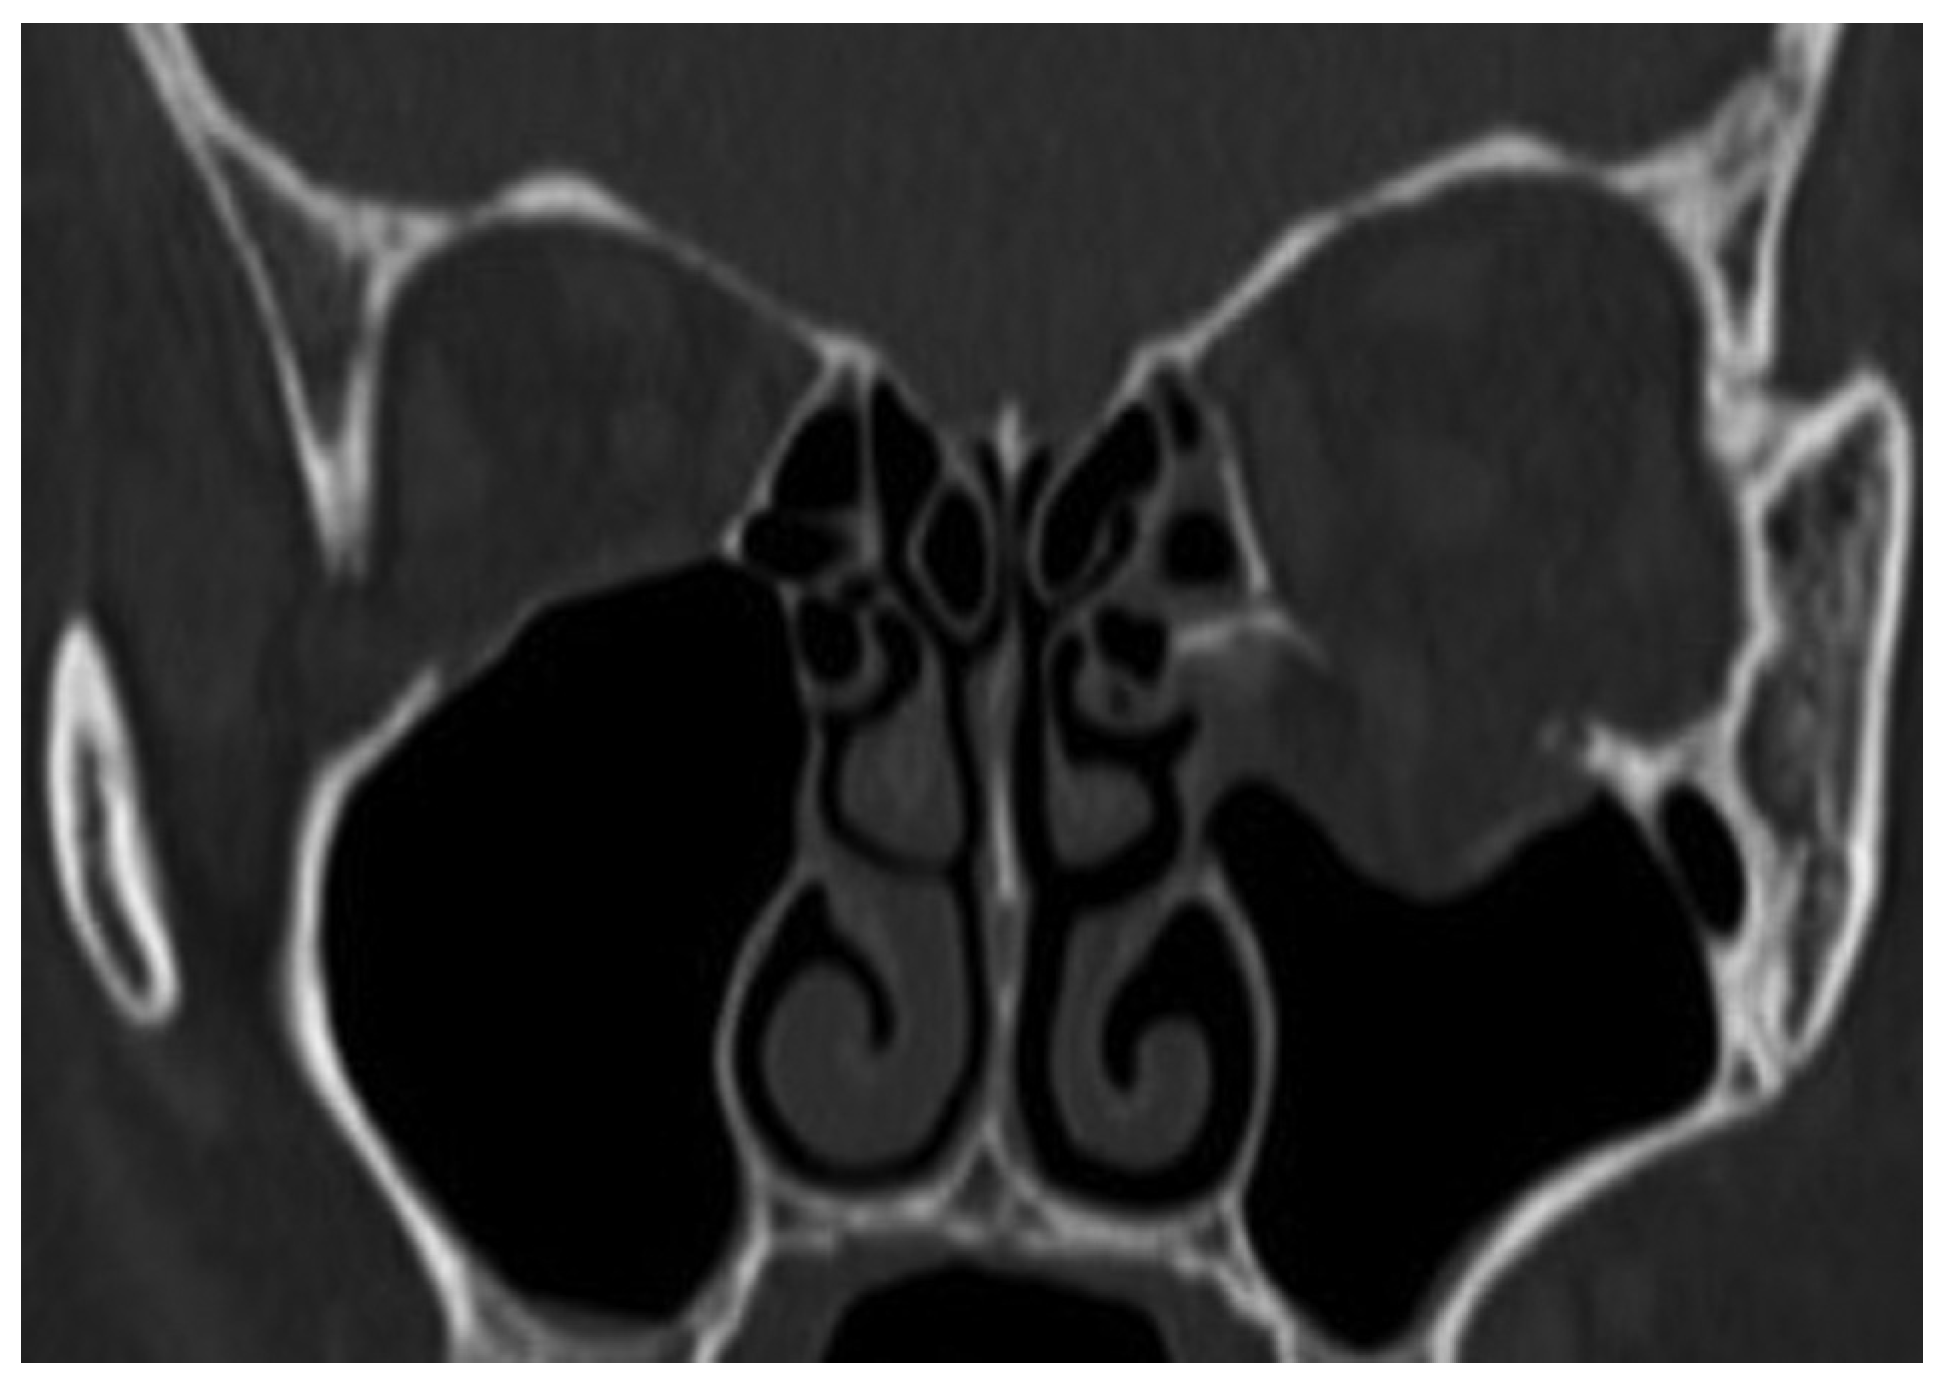

Case 12

A 39-year-old woman sustained facial injuries, and presented with diplopia. She was referred to our clinic by an ophthalmologist for a suspected blowout fracture at 3 weeks after injury. A CT scan revealed bone defect of orbital floor and the displacement of soft tissue into the maxillary (Figure 3). The patient’s left eye movements—up gaze and down gaze—were severely restricted (Figure 4). The diagnosis was a blowout fracture with the orbital floor punched out. Forced duction testing was performed at the beginning of the case to document any preoperative globe restriction. The surgery was performed to reconstruct the orbital floor at 27 days after injury. By transconjunctival approach, the orbital fat and muscle was pulled into the floor cavity, and a 35 mm × 20 mm defect of the orbital floor was seen. A graft was harvested from the sixth right-side rib by splitting it in situ at the size of 50 mm × 15 mm. The split bone was cut and remade into a double leaf using absorbable suture, and gently inserted into the orbital floor without fixation.

Tarsorrhaphy was done and kept for 1 day to prevent the swelling of conjunctiva, and the exercise of eye movements started soon. Coronal CT after surgery revealed good position of the bone graft to orbital floor at 4 weeks after surgery (Figure 5). The diplopia was rectified completely in 7 weeks after surgery (Figure 6).

Figure 5. Coronal view of CT after surgery.